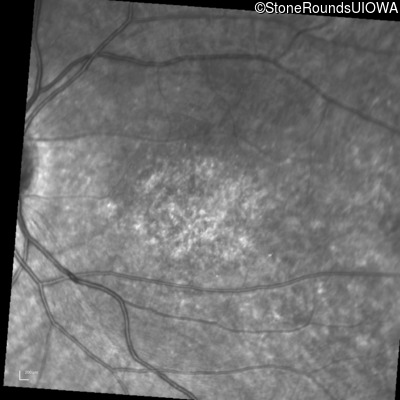

Infrared Fundus Photograph - Right - 10/140 sc

Exemplar

Infrared Fundus Photograph - Left - 10/200 sc